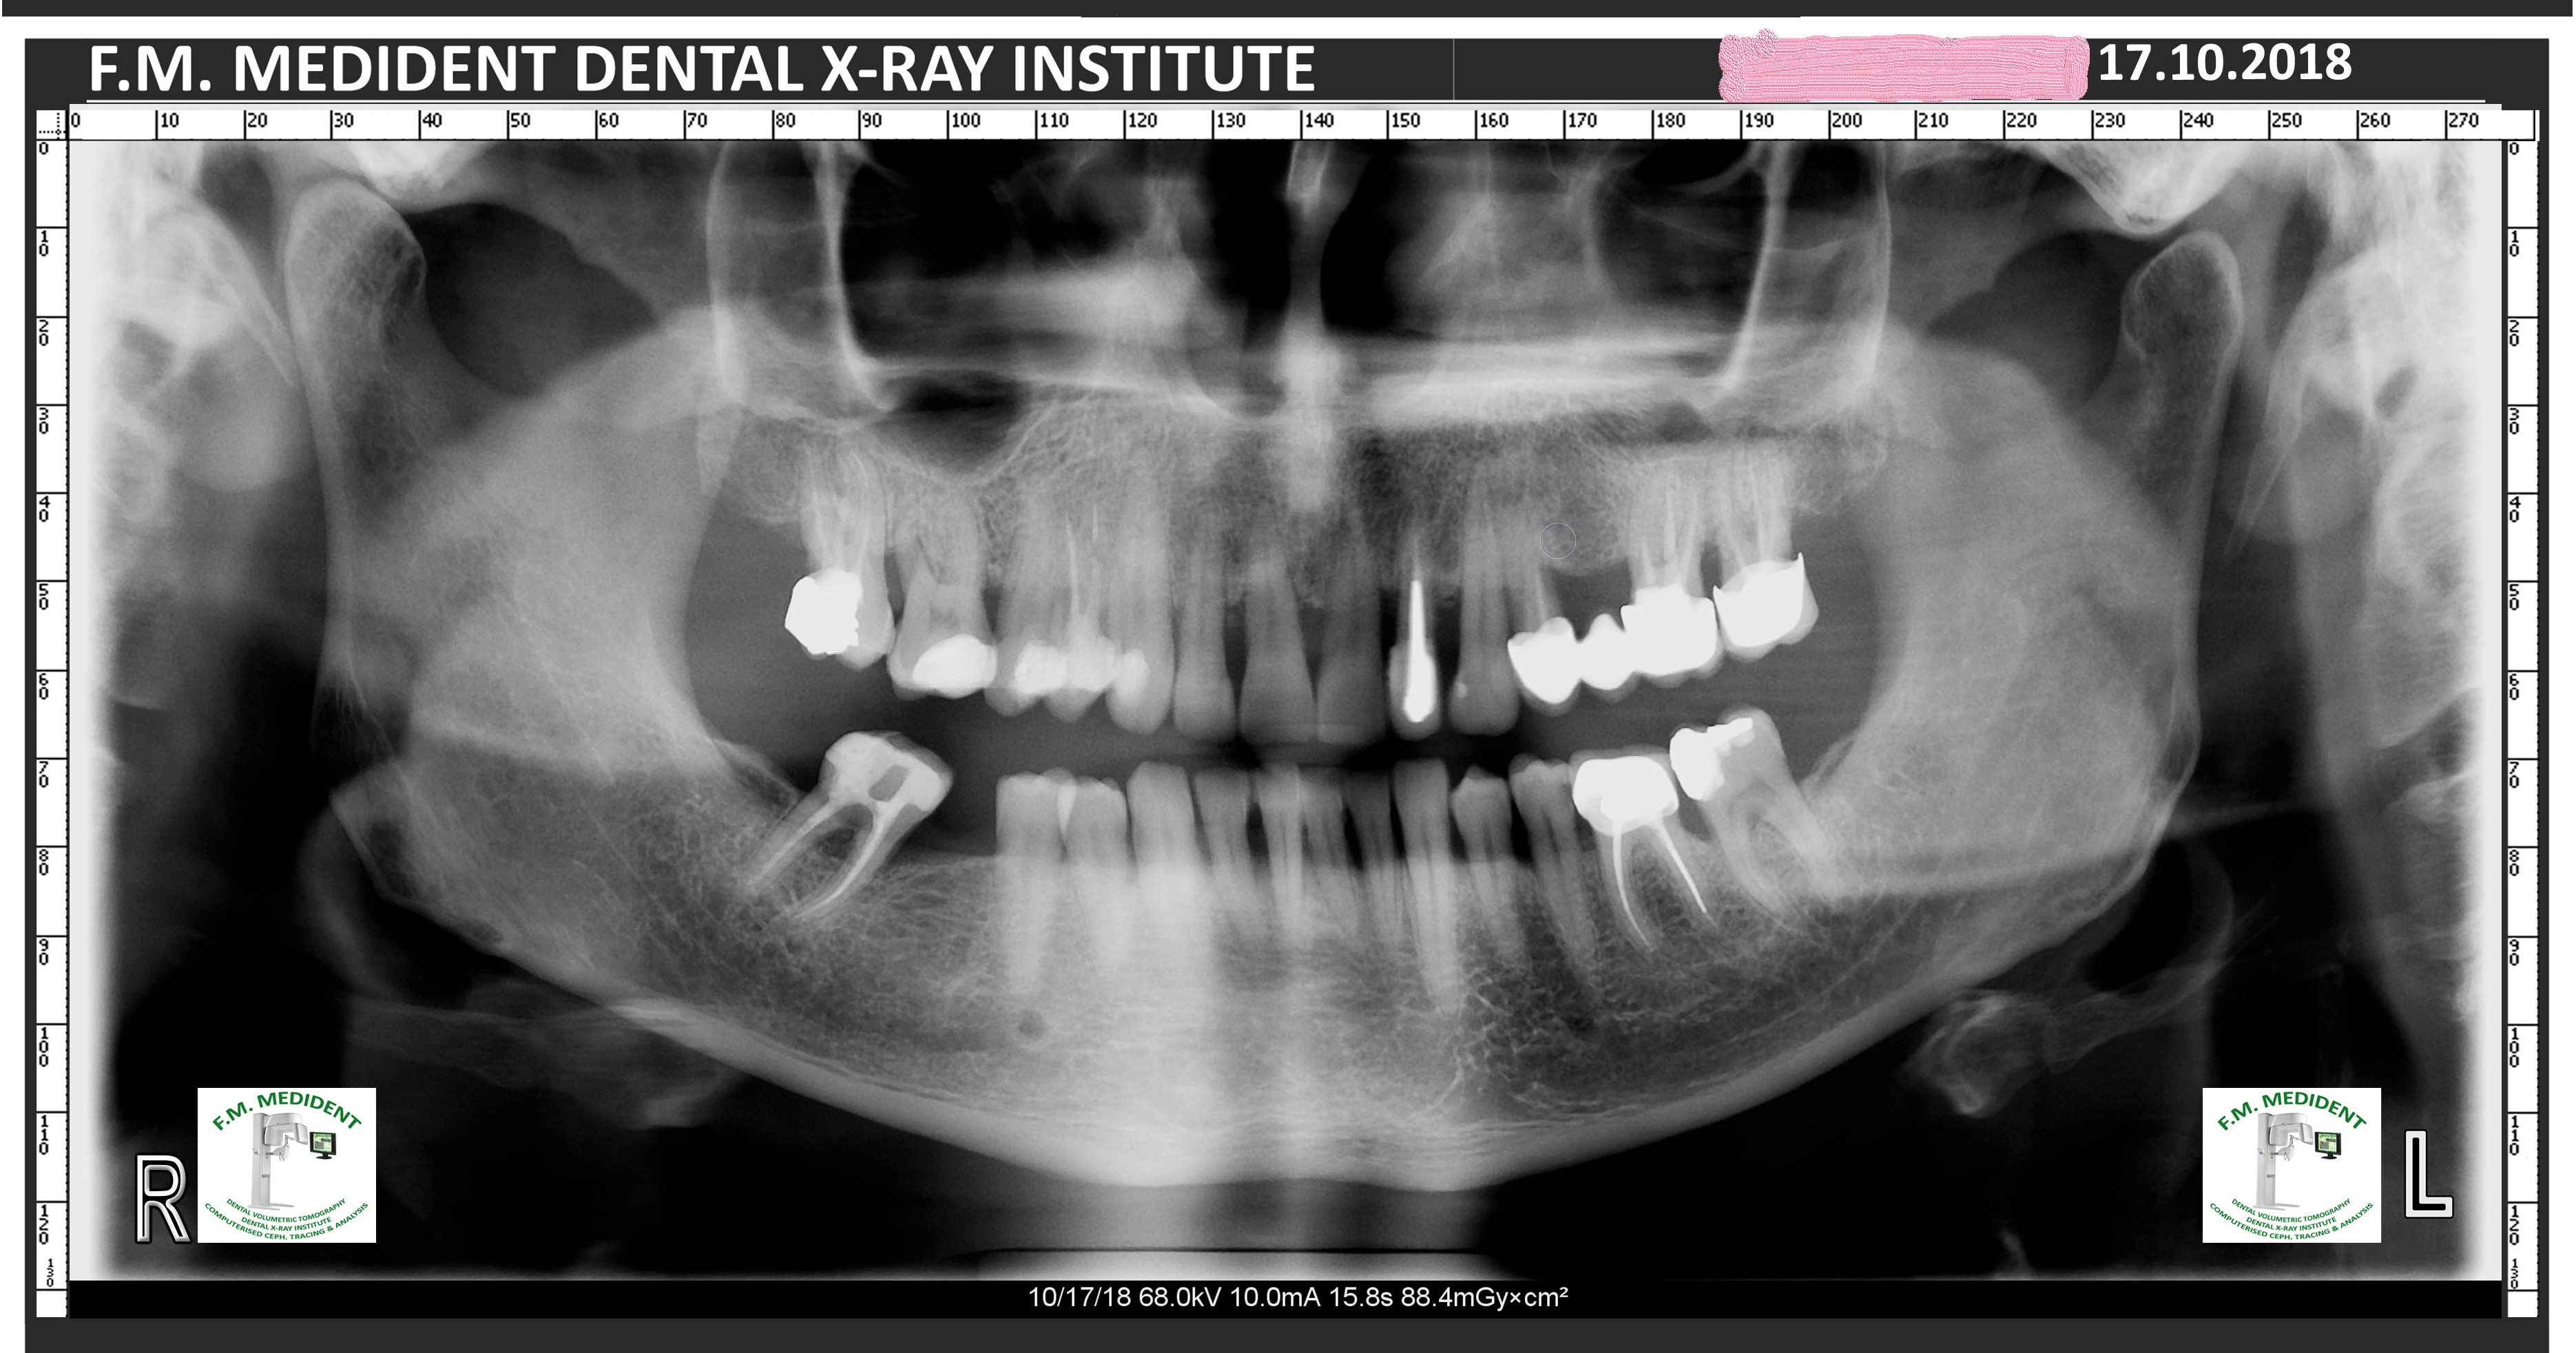

Atașez pozele unui pacient care până la vârsta de 44 ani nu a fost niciodată la dentist, cu reflex de vomă exagerat și igienă deficitară, speriat că i s-a propus extracția a peste 50% din dinți din cauza mobilității generalizate de gradul II și III. Am mers pe varianta clasică, debridare parodontală nechirurgicală, la microscop, cu anestezie locala în toate cadranele, realizată într-o singură ședință. Am administrat antibiotic pe cale generală și am urmărit respectarea indicațiilor de igienă prin controale lunare. Rezultatele la 6 luni vorbesc de la sine, acum putând să ne ocupam liniștiți de regenerarea defectelor osoase de la nivelul 21 22, de altfel singurii dinți care mai au mobilitate.

Iar retracția de la 31 s-a vindecat singură 🙂 Pentru că timpul e, uneori, cel mai bun tratament.